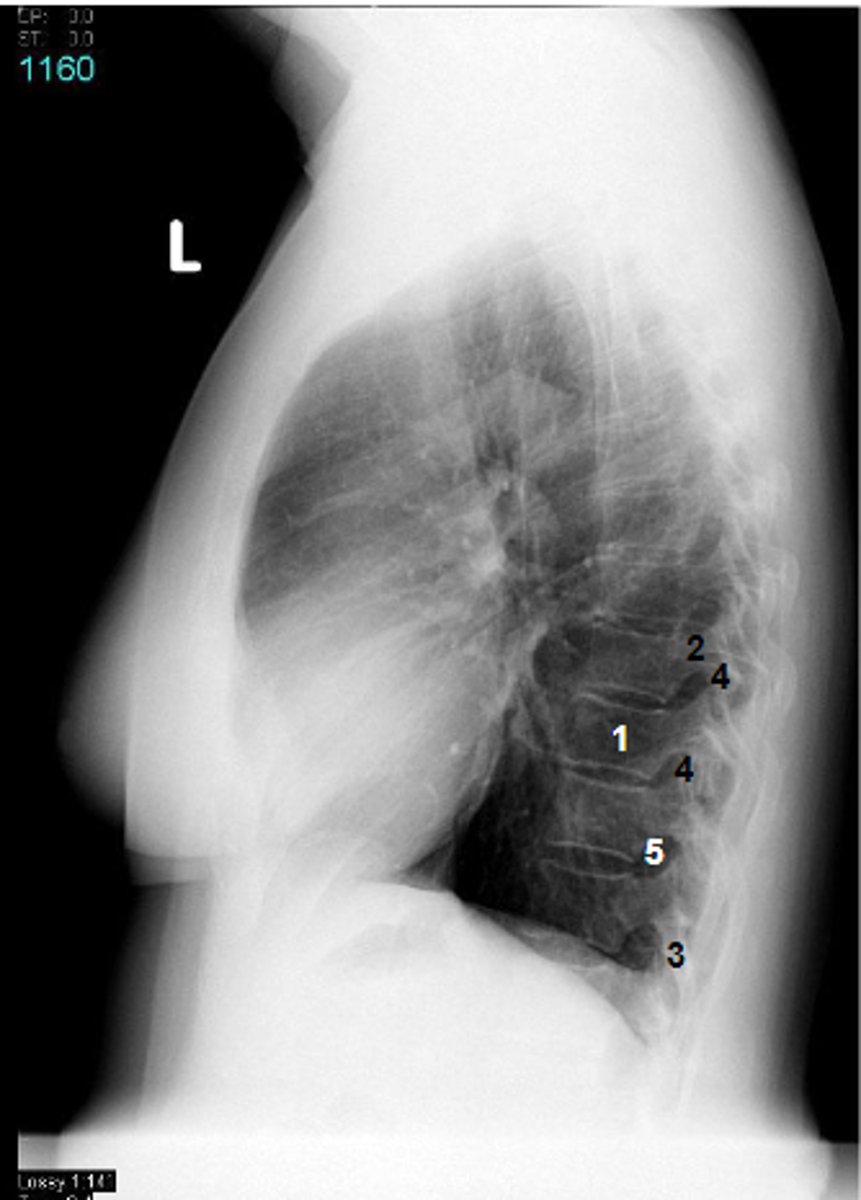

1

at what number is the body

2

at what number is the pedicle

3

at what number is the spinous process

4

at what number is the articular process

5

at what number is the intervertebral foramen